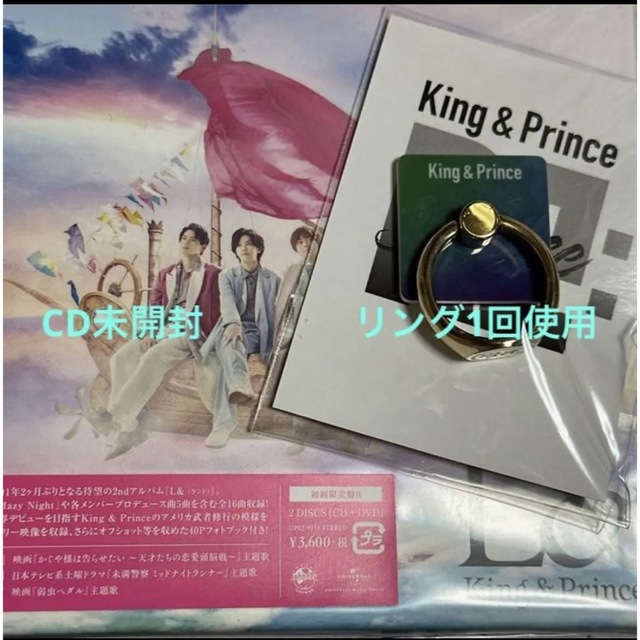

■商品名■

ThyroidCancerExploreVol.1No

■出版社■

メディカルレビュー社

■著者■

「ThyroidCancerExpl

■発行年■

2015/09/01

■ISBN10■

4779215277

■ISBN13■

9784779215278

■コンディションランク■

非常に良い

コンディションランク説明

ほぼ新品:未使用に近い状態の商品

非常に良い:傷や汚れが少なくきれいな状態の商品

良い:多少の傷や汚れがあるが、概ね良好な状態の商品(中古品として並の状態の商品)

可:傷や汚れが目立つものの、使用には問題ない状態の商品

■コンディション詳細■

書き込みありません。弊社基準で良よりコンデションが良いと判断された商品となります。